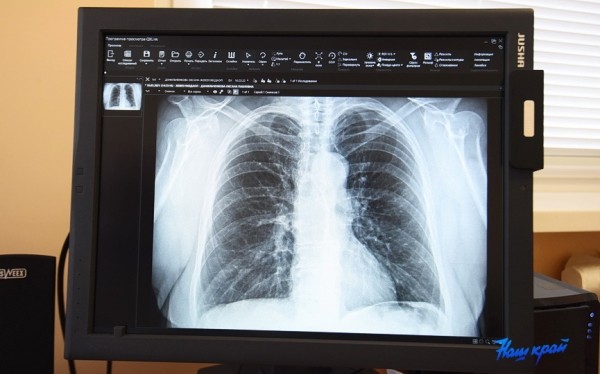

Туберкулез на ранних стадиях часто никак себя не проявляет, поэтому всему населению следует своевременно проходить рентгенофлюорографическое обследование. А для снижения риска заражения и развития заболевания необходимо укреплять свой организм и вести здоровый образ жизни.